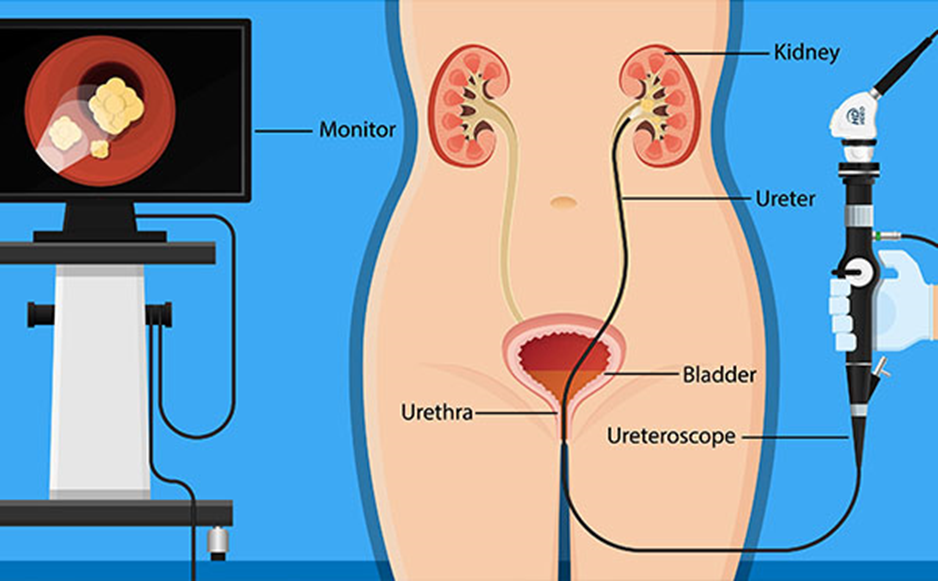

Traitement interventionnel :

- L’urétéroscopie laser

Est une Intervention endoscopique mini-invasive utilisée pour traiter les calculs rénaux et urinaires, en particulier dans l’uretère et le rein. Un urétéroscope, instrument souple ou semi-rigide, est introduit par les voies naturelles pour atteindre le calcul. Le laser est ensuite utilisé pour fragmenter le calcul en plus petits morceaux, qui peuvent être évacués spontanément par la suite.